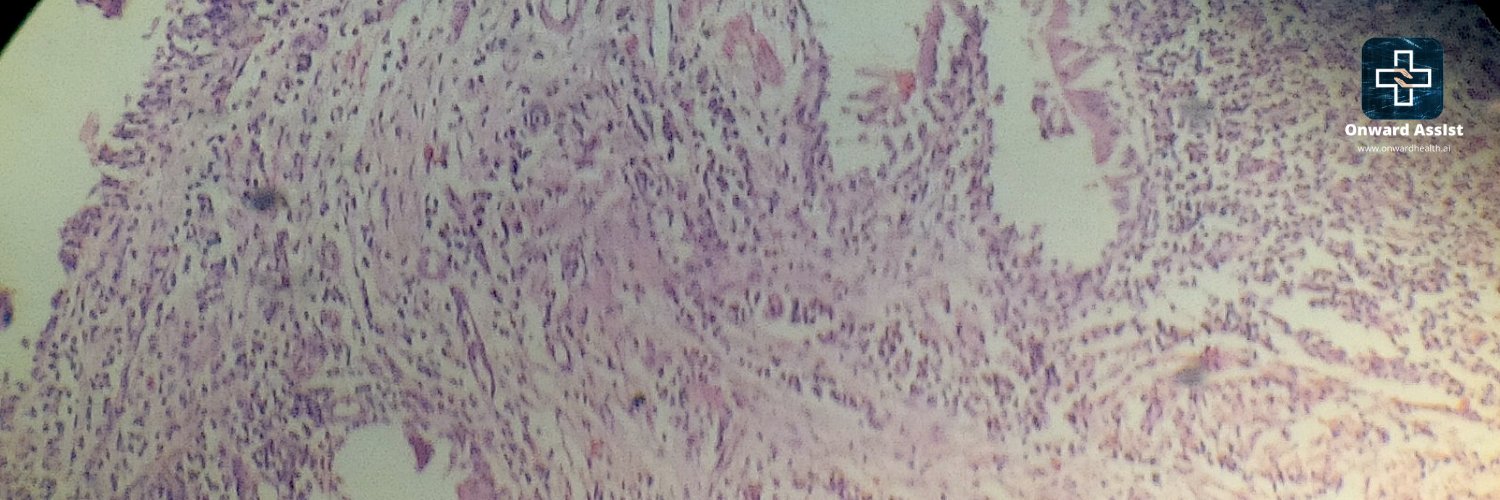

Cancer analytics platform helping make better treatment decisions. # ComputationalPathology, Assisting better clinical decisions. Leveraging #ML #CV